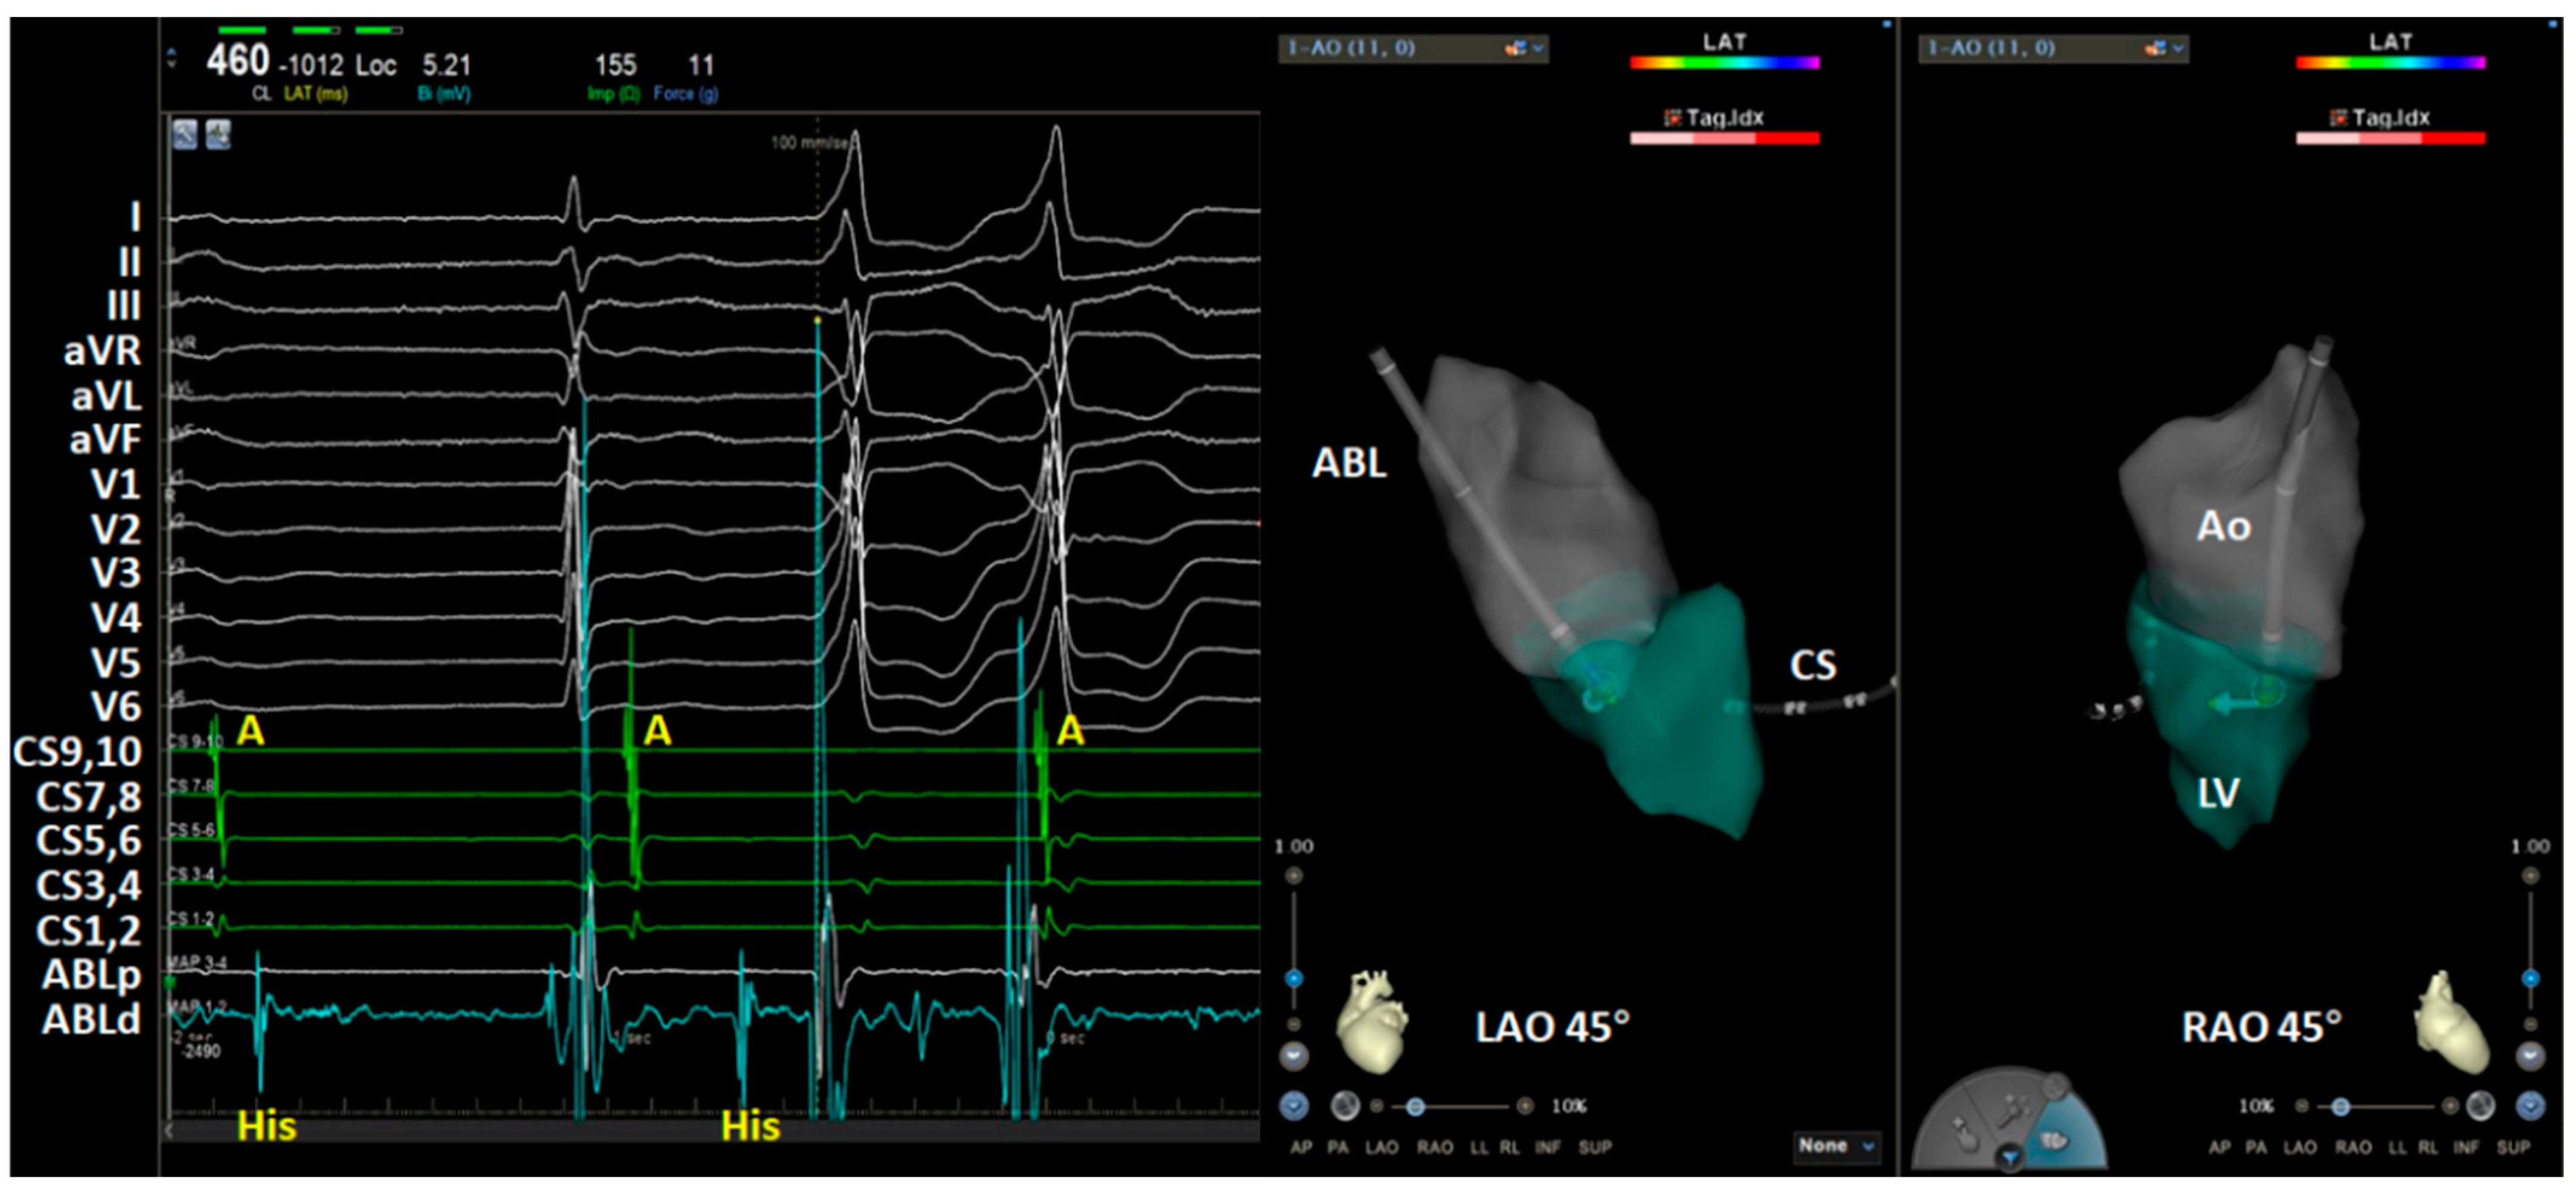

2. Case Report